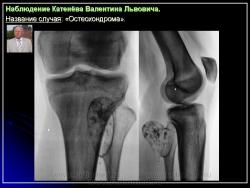

Остеохондрома (костно-хрящевой экзостоз).

Наблюдение Катенёва В.Л.

Приложения:

1.201607190013.jpg2.201607190017.jpg3.201607190018.jpg4.201607190016.jpg5.201607190019.jpg6.201607190020.jpg7.201607190021.jpg